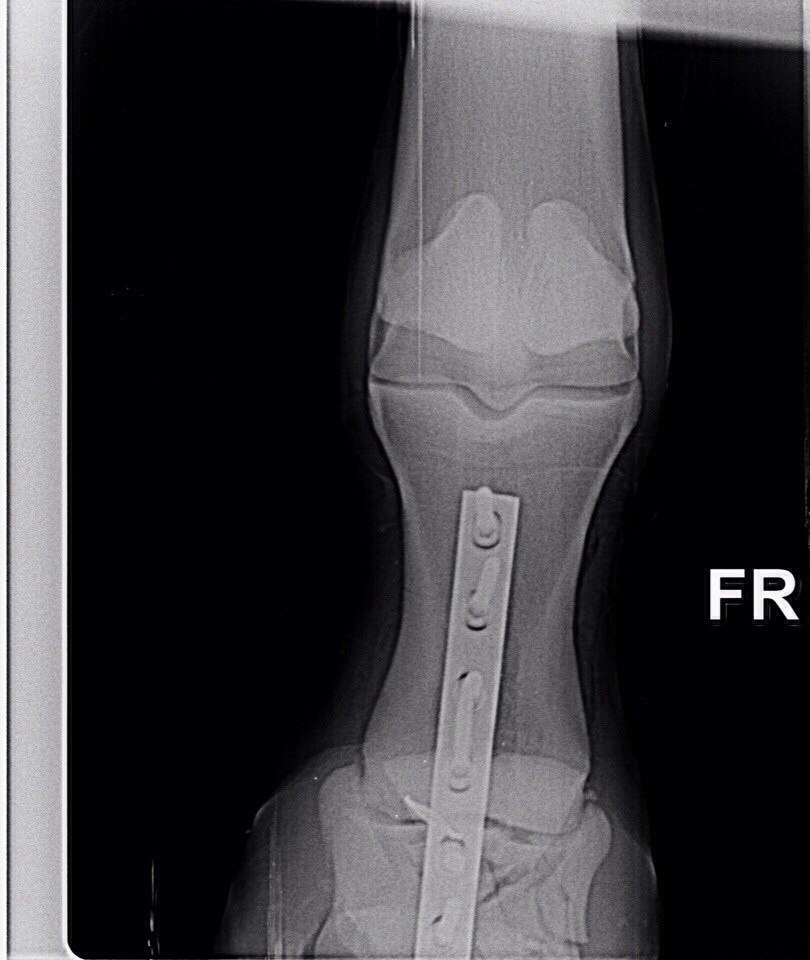

Жеребец. Винтовой перелом путовой кости на ЛЗ почти по всей её длине, внизу перелома смещение 5 отломков.

Брался НВ - остеосинтез на пластины и штифты. перегипсовка каждые определенные периоды. Наложение гипса при таких переломах отличается на передней ноге получен перелом или задней. На задней сложнее. Нужен наркоз каждый раз.

Стоял с гипсом 2,5 месяца, постоянные рентгены, жрал кучу всего. Гипс он как-то так продавил пяткой или что еще сделал, но получился, как костыль, на который он мог опираться и как-то даже перемещался по деннику. Сразу научился ложиться, вытягивая ногу и также вставать. Он сразу хотел жить и делал всё от него зависящее. Вот в этот период у него было отличное дыхание, что вообще никто не может объяснить.

Делающие рентгены ветеринары (Отрада, Эквимедика) говорили, что его случай противоречит медицинской практике и опыту. И что это магия

На месте сращения отломков образовалась шишка, предупредили, что это жабка (вроде так) и она может расти дальше.

Лошадка имеет свои особенности сейчас по поддержке артроза. Но не ужас-ужас. Как обычный хроник по ногам. Хобл доставляет гораздо больше хлопот. Живет полноценной жизнью. Играет, пинается, порой при его хорошем настроении может показать всаднику в поле, что 15/16 крови чк это не хухры-мухры